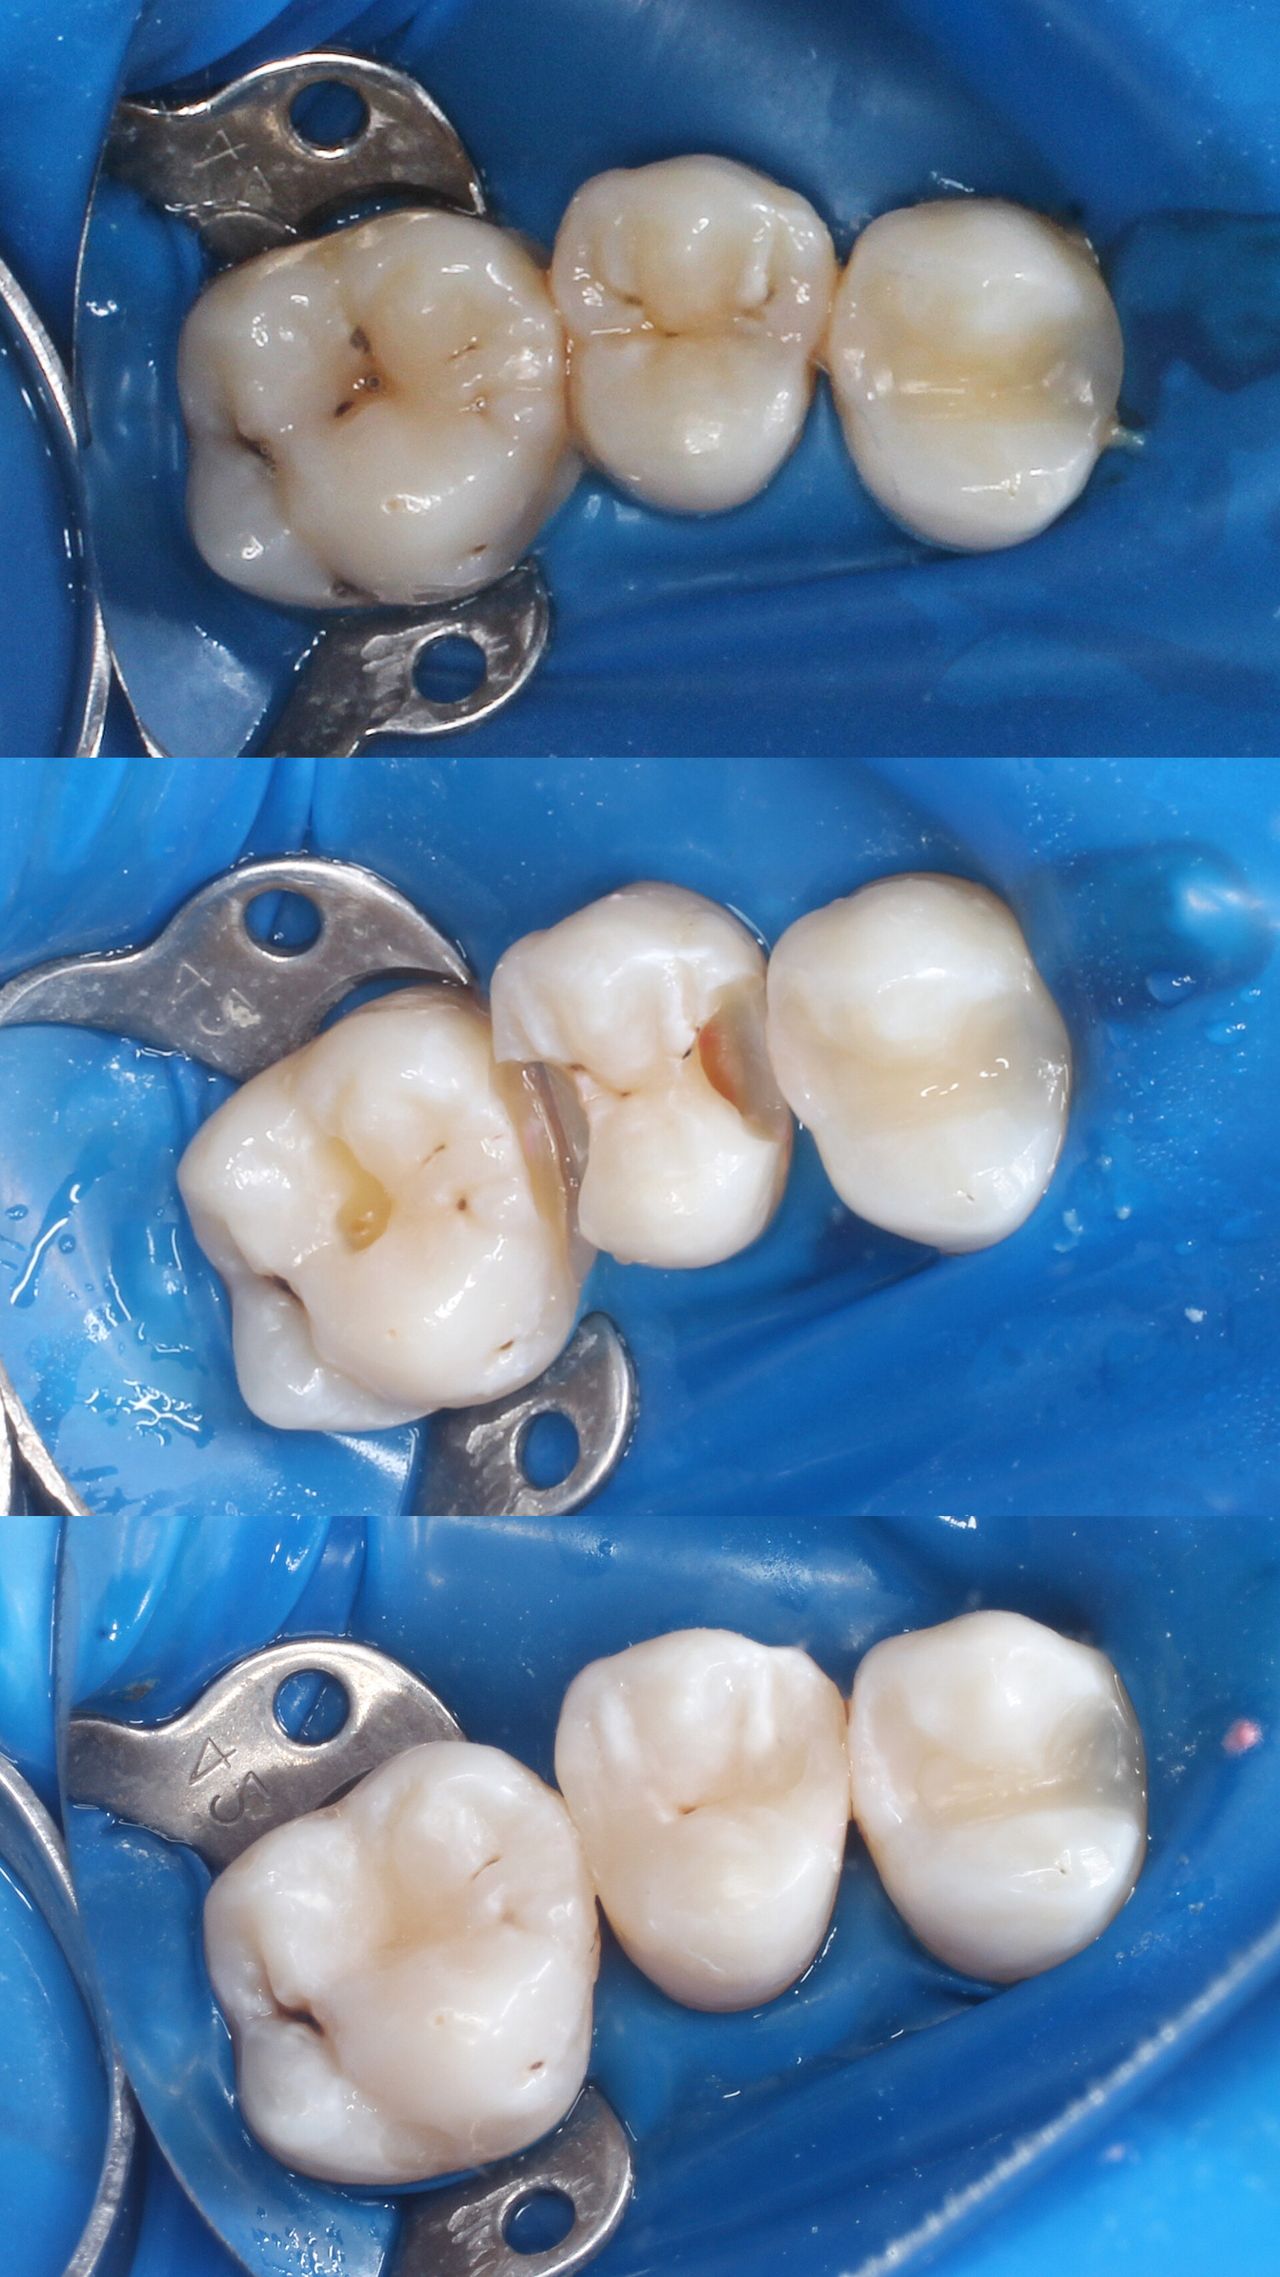

Na co dzień zajmuję się głównie stomatologią zachowawczą oraz leczeniem endodontycznym z wykorzystaniem mikroskopu. Wykonuję leczenie próchnicy i jej powikłań zarówno u dorosłych, jak i u dzieci. Zajmuję się również zabiegami higienizacji, wybielaniem zębów, leczeniem niepróchnicowych zmian szkliwa metodą ICON

Zdjęcia i filmy